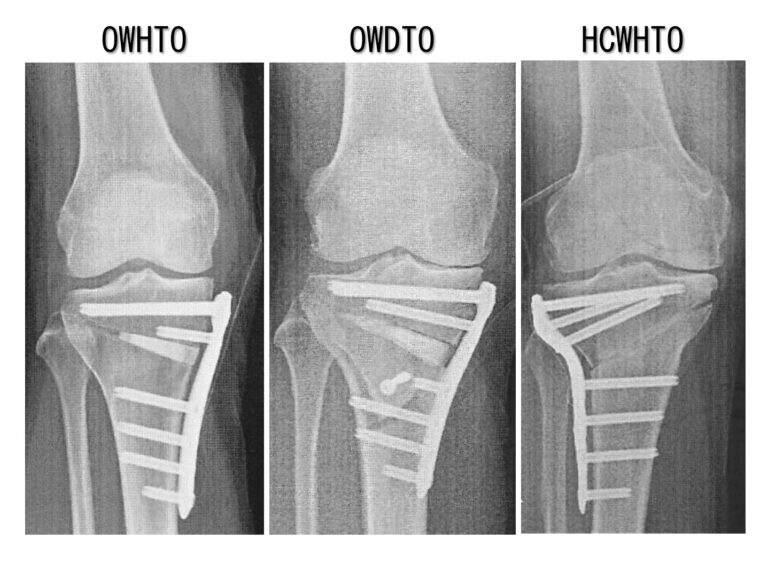

HTOの各術式の特徴

HTOにはopen wedgeとclose wedge2種類の方法があります。

①open wedge

脛骨の内側から外に向かって骨を切り、内側を開いて隙間に人工骨をいれます。侵襲や合併症が少なく第一選択ですが、矯正角度に限界があります。

②close wedge

脛骨の外側から骨を楔状に切って切除して隙間を埋めます。多少侵襲が大きくなりますが(腓骨も切ります)角度の大きな矯正も可能です。

OWDTOの特徴

脛骨の骨切りに対して、脛骨粗面の遠位側で円弧状に骨切りします。

PF関節の位置が変わりません。

膝蓋骨低位がおきません。

膝蓋腱周囲に侵襲がありません。

デメリット

脛骨粗面に固定スクリュー1本追加

後療法をやや遅らせます(免荷1週)。

HCWHTOの特徴

メリット

大きな矯正角度にも対応可能

やや侵襲が大きくなります。

腓骨の骨切りが必要

後療法を遅らせます(免荷1〜2週)。